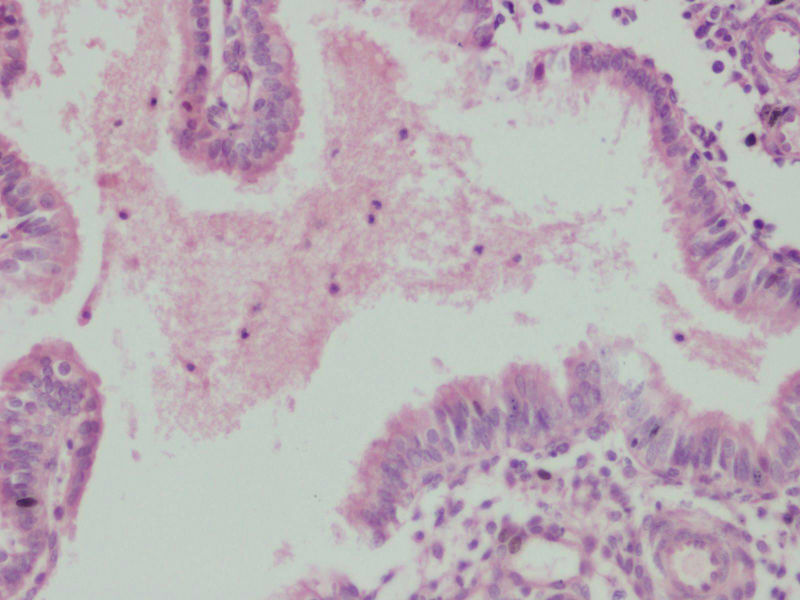

图1

女44,阴道不规则流血一月

流血期宫内膜